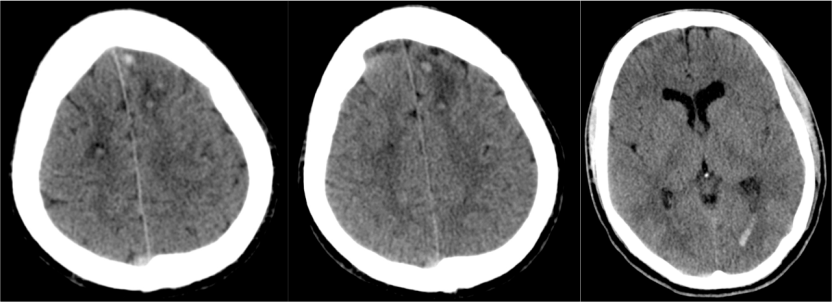

Hallazgos TC:

- En fase aguda puede ser Nomal.

- Edema cerebral (borramiento de surcos)

- Focos hemorrágicos en las sitios anteriomente descritos

- En fase cronica = zonas hipodensas + atrofia.

1- Edema cerebral difuso: Aparece en las primeras 48 horas del traumatismo. Se identifica por:

- Produce efecto de masa.

- Borramiento de surcos = pérdida de la interfase sustancia gris-sustancia blanca.

- Otros: signo del cerebelo blanco, falsa hemorragia subaracnoidea…